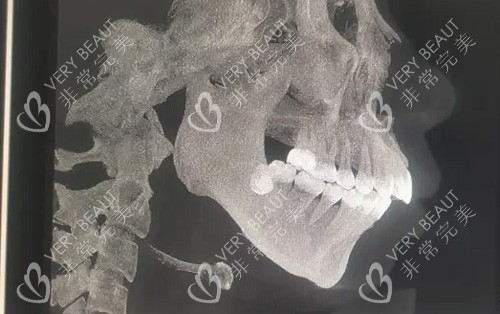

需要做正颌手术的骨骼图

面诊时,何锦泉医生仔细检查了我的面部情况,分析了初次手术失败的原因。他解释说,正颌手术是复杂的四级外科手术,需要极高的精度,微小的偏差都可能导致术后嘴巴歪斜。何医生采用CT精细扫描测量了我的颌面数据,运用3D智能系统进行计算机辅助设计,为制定修复方案提供了***依据。